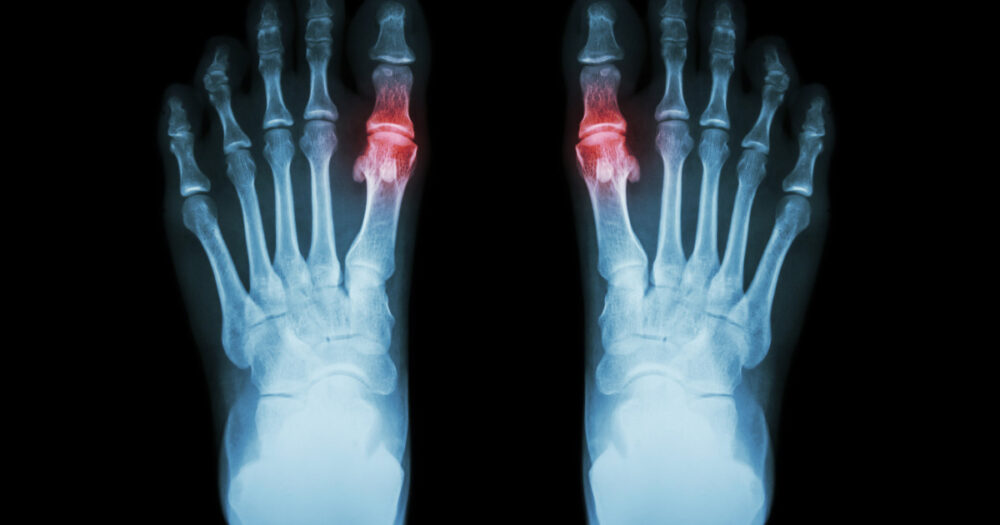

“Gout is a type of inflammatory arthritis that causes pain and swelling in the joints,” explains Clayton Keene, a nurse practitioner at Aurora Family Medicine in Oconto, Wis. “It occurs when high levels of urate accumulate in the body, which then forms crystals in and around joints.”

“The most common symptom of gout is pain in the affected joint,” Keene advises. “Most people have their first flare of gout in the big toe; however, it can occur in other joints, too. Symptoms include increased pain, redness, swelling and stiffness.”

- X-ray: Can rule out other causes of joint inflammation.